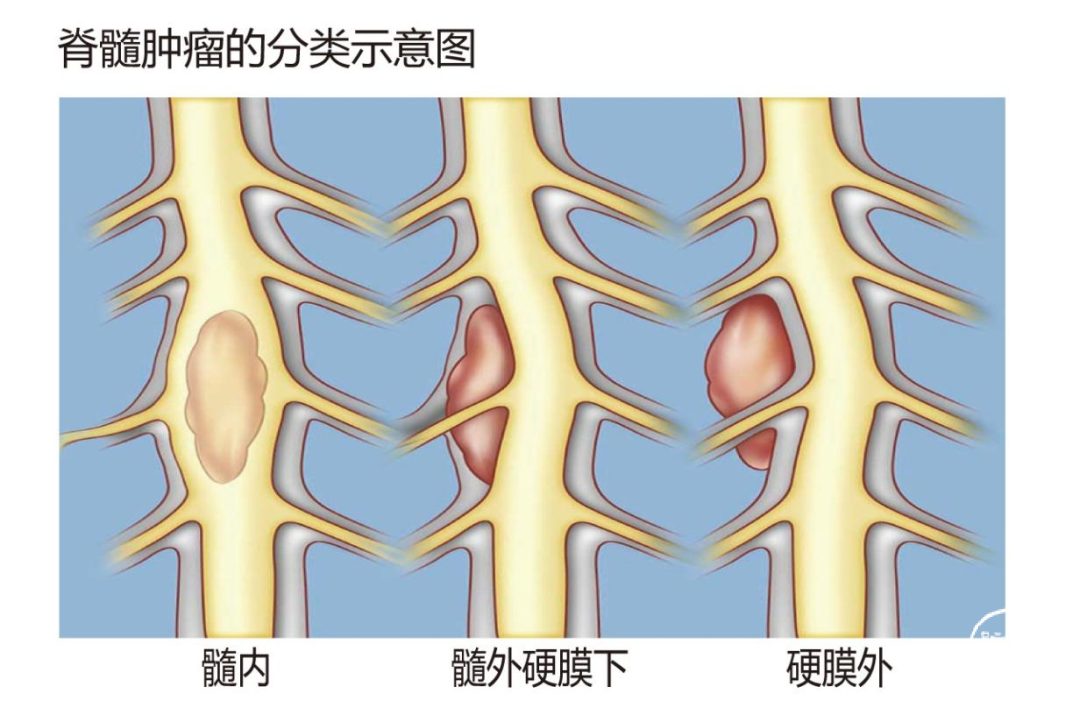

10

脊柱内固定技术是一种通过植入内固定物(如椎弓根螺钉、钛棒等)来稳定脊柱的技术。在高颈段椎管内肿瘤和椎管内外沟通性肿瘤的手术切除后,如果脊柱稳定性受到破坏,就需要进行脊柱内固定。高颈段椎管内肿瘤和椎管内外沟通性肿瘤的手术切除及脊柱内固定技术是一项复杂而精细的手术过程,可以在最大限度地切除肿瘤的同时一期重建脊柱的稳定性,从而改善患者的预后和生活质量。